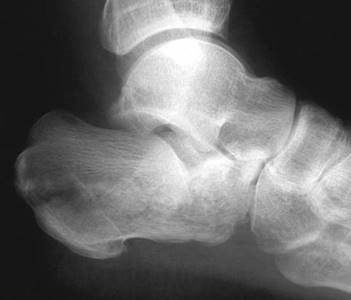

What do you see and which joint is involved?

This AP radiograph shows disruption at the tarso-metatarsal joints otherwise known as a Lisfranc injury.

What is the Lisfranc joint?

This consists of three cuneiform and two cuboid metatarsal articulations. Joint stability is provided by strong ligaments and the recessing of the second metatarsal head. The Lisfranc ligament runs from the base of the second metatarsal to the medial cuneiform.

How do you describe Lisfranc injuries and which type is this?

T ype A is a complete uniplanar dislocation involving the whole joint. A type B injury describes a partial dislocation, either medial or lateral. Type C injuries are divergent dislocations.

In this case there appears to be a lateral type B injury.

This is an isolated injury. How would you proceed?

I would provide analgesia and elevation with a resting splint, including foot/ankle, but allowing room for swelling. I would observe for evidence of compartment syndrome and obtain further radiographic views and CT scan. I would wait for the swelling to reduce before considering surgery. Skin softening and wrinkling suggests that swelling is receding.

What do you look for on plain radiographs?

O n an AP view the second metatarsal and medial cuneiform medial borders should align. On an oblique view the medial borders of the fourth metatarsal and cuboid should align. I would also look for the fl eck sign which implies an avulsion of the Lisfranc ligament.

What is your operative plan for this fracture?

I would plan to openly reduce and fi x with screws, starting with the second metatarsal reduction. I would employ two skin incisions, one over the fi rst web space, the second over the fourth metatarsal.

What are you going to say to this patient about his long-term outcome?

I would warn him that even if his surgery goes well and things heal as planned there remains a 30 % chance of post-traumatic osteoarthritis.